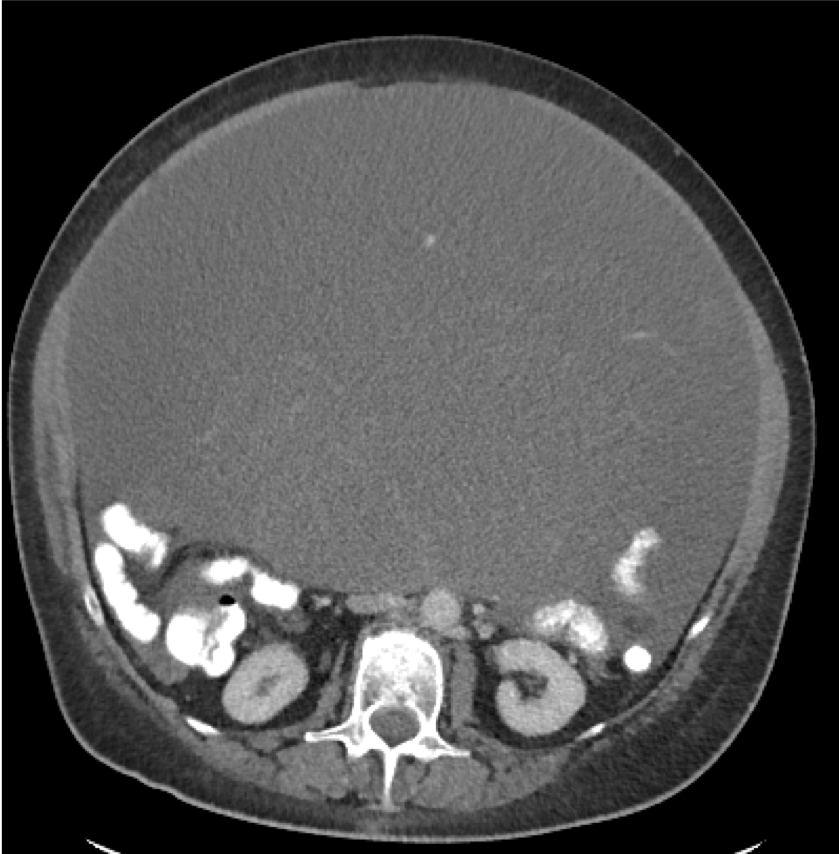

A 56-year-old woman presents for evaluation of increasing abdominal girth, fullness, and abdominal pain. On examination, her abdomen is distended and she has had progressive weight loss of 50 lbs over the last 1 year. Computed tomography is performed (Figure). Her gynecologic examination and transvaginal ultrasonography findings are normal. Findings of colonoscopy are unremarkable. What is the best step in management?